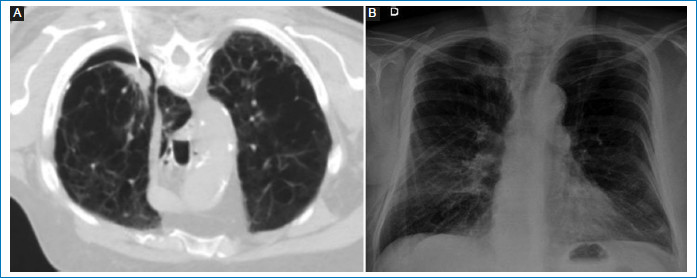

Como dato adicional, de los pacientes que presentaron esta complicación solo dos (14%) requirieron la colocación de un tubo de avenamiento pleural para el tratamiento de neumotórax. Ambos presentaban enfisema, uno con características cualitativas de enfisema confluente/avanzado, a quien se le extrajo el tubo 10 días luego del procedimiento, considerado como efecto adverso mayor; y el otro enfisema leve, y se le retiró el tubo a las 48 horas, considerado como efecto adverso menor. Los dos pacientes fueron controlados con radiografías de tórax y no presentaron otras complicaciones (Figs. 2 A y B).

Del total de los pacientes que desarrollaron neumotórax, el 14%, correspondiente a dos casos, necesitaron tubo de avenamiento pleural, y aquel clasificado como evento adverso mayor debido a mayor estadía hospitalaria presentaba signos más graves de enfisema. Es probable que el mayor porcentaje de colocación de tubo pleural que el demostrado en la literatura se deba a un menor tamaño muestral. Sin embargo, coincidente con la literatura, en nuestro estudio, el neumotórax y la hemorragia alveolar, que es otra complicación frecuente, se resolvieron espontáneamente, con un pequeño porcentaje de pacientes que requirieron la colocación de tubo pleural, por lo que podemos decir que la TCMD sigue siendo un procedimiento seguro6,12,13.